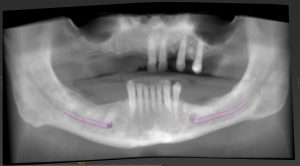

Case Study: Guided All-on-6 Rehabilitation with MagnetiX™

A recent case by Dr. Curry Leavitt, DMD, illustrates the power of guided workflows in All-on-X treatment.

A 76-year-old male presented with generalized caries and fractured, non-restorable maxillary teeth. His chief complaint was esthetics and difficulty in chewing.

Digital Planning with 3DDX

- A CBCT scan was taken and uploaded to 3DDX

- The treatment planning team used coDiagnostiX® software to position six implants in the maxillary arch.

- Intraoral impressions and clinical photos were integrated for digital smile design and prosthetic planning.